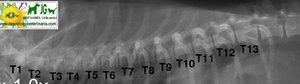

vértebras torácicas caninas |

Radiografía laterolateral de la columna torácica canina |